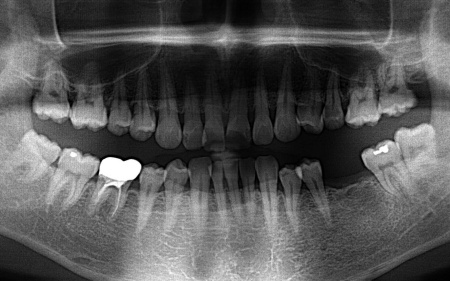

治療前

| 診断 | 拝見したところ、左下奥歯(第1大臼歯)が抜けており、見た目が気になるだけでなく奥歯でしっかりと噛むことが難しくなっていました。 このまま放置すると食事の際に支障が出たり、噛み合わせのバランスが崩れて残っているほかの歯に影響を及ぼしたりする可能性があります。 以上のことから、抜けた歯を補い見た目と噛む機能を回復させる治療が必要と診断しました。 |

| 行ったご提案・治療内容 | 患者様はあごの骨に人工歯根を埋め、その上に人工歯を装着するインプラント治療を希望されています。 インプラント治療は自分の歯のような自然な見た目と噛み心地が期待できる一方で、自費診療のため費用が高くなることや外科処置を伴うため身体的負担がかかること、治療期間が比較的長くなる点がデメリットです。 また、安定したインプラント治療を行うためにはインプラントを支えられるあごの骨が残っているか、インプラントの上に人工歯を取り付けた際に噛み合わせの歯が邪魔をしないかなどを確認する必要があります。 その結果、十分な骨の量があり、噛み合わせの歯もインプラントを入れた際に自然に噛める位置に生えていたため、インプラント治療を行う条件は問題ないと判断しました。 【治療手順】 最後に見た目や噛み合わせに問題がないことを確認し、治療を終了しました。 |